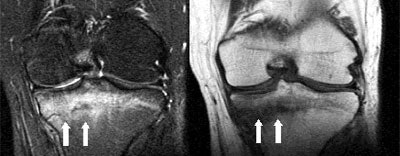

| Coronal T1 (left) and T2 (right) MR images show the linear fracture within the metaphyseal tibia (white arrows). The fracture was surrounded by a substantial amount of bone marrow edema, seen best as the bright signal on the T2-weighted image. Images courtesy of Dr. Douglas P. Beall. |